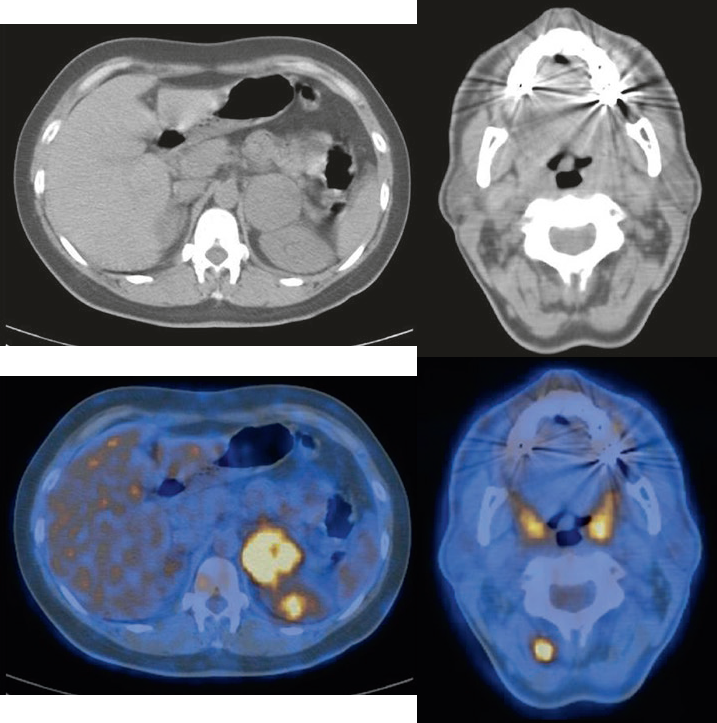

Melanoma del braccio sinistro operato con massa surrenale sospetta alla TC.

Aumento dell’assorbimento in una massa surrenale sinistra e in un linfonodo nucale destro. La PET è utile per la ristadiazione dei pazienti con sospetta recidiva di melanoma.